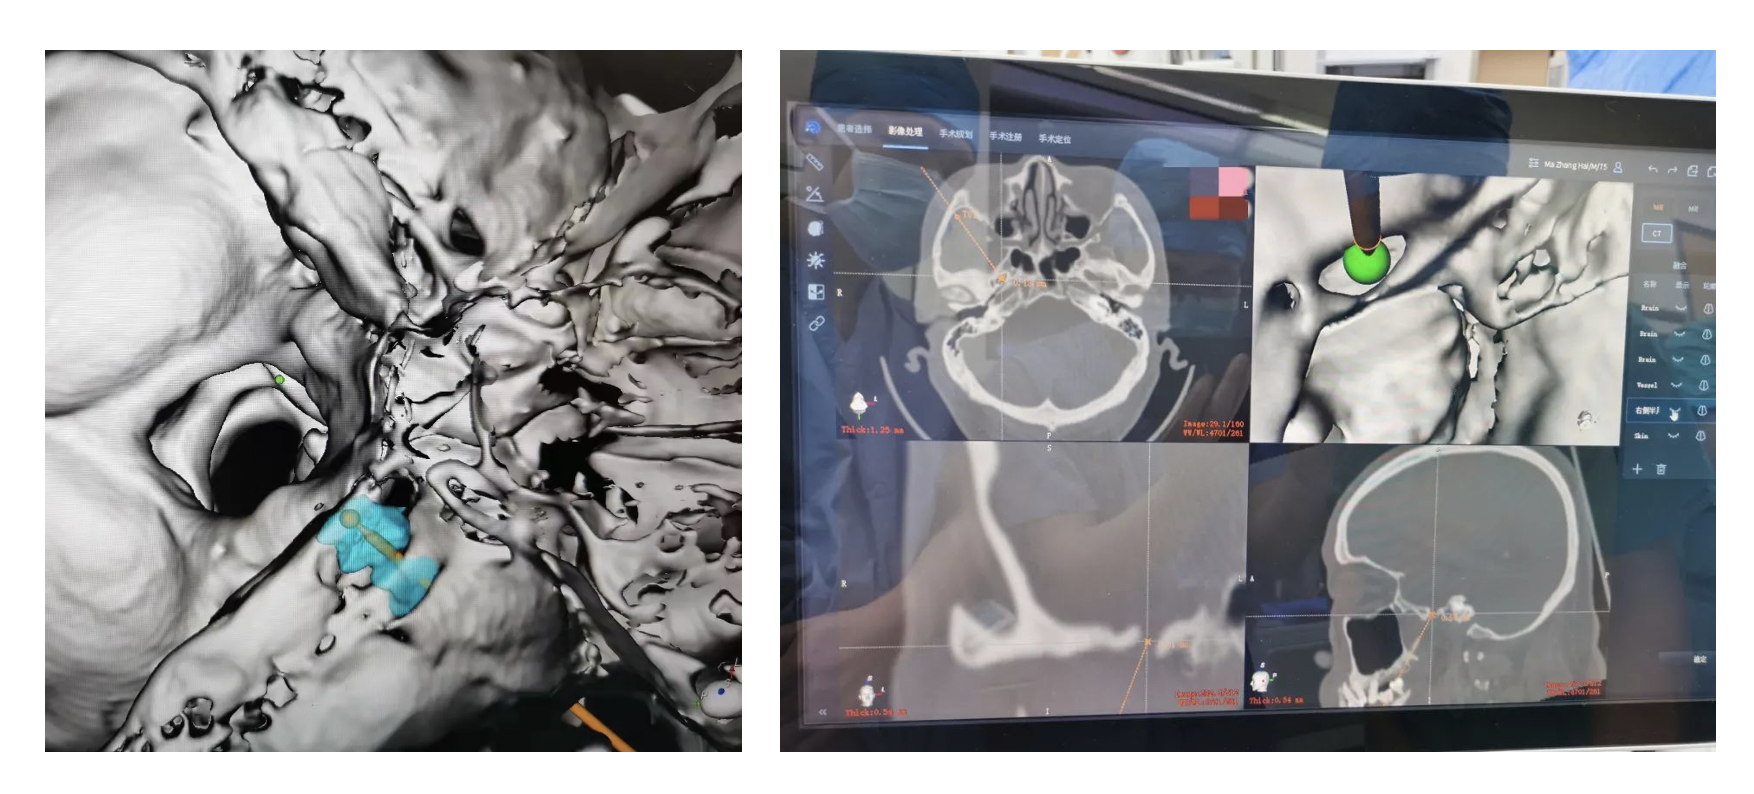

The picture shows two cases of trigeminal neuralgia treated by robot-guided balloon compression of trigeminal semilunar node in department of neurosurgery of Xuanwu Hospital. All patients were of elder age, with long onset time and poor drug control effect, which had a great impact on quality of life. The robot surgery can precisely localize the puncture location and depth in real time, understand the surrounding adjacent structure, ensure the safety of surgery, postoperative pain relief immediately, 3 days after discharge, achieve a satisfactory curative effect.